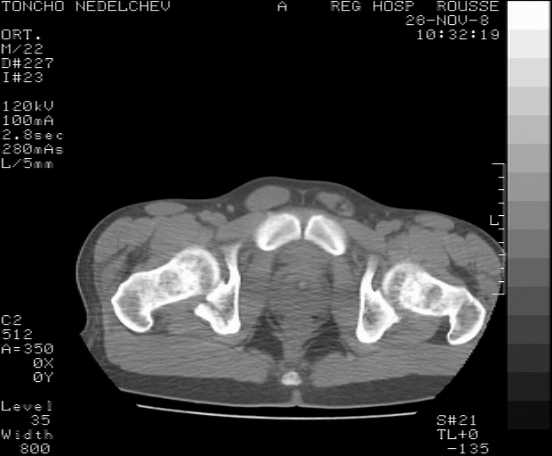

The details of the fracture are not so clear from the images sent...would you be able to send along an AP and Judet images as well as some additional axial images above and below the joint?

I’m not so sure that your patient has a Tr+PW pattern based on the images sent...maybe the fracture’s exact name won’t matter in the long run, but it’d be great to see enough images to make an accurate comment.

Without complete CT images and/or oblique radiographs, it's difficult to answer your question definitively, but it appears that there may not be a posterior wall fracture that requires a posterior approach. A successful reduction through an ilio-inguinal approach will have a faster recovery, and not risk SGN injury or heterotopic ossification.

Here are some more axial images. What is your opinion as for the timing of the operative treatment?

posterior approach, ORIF